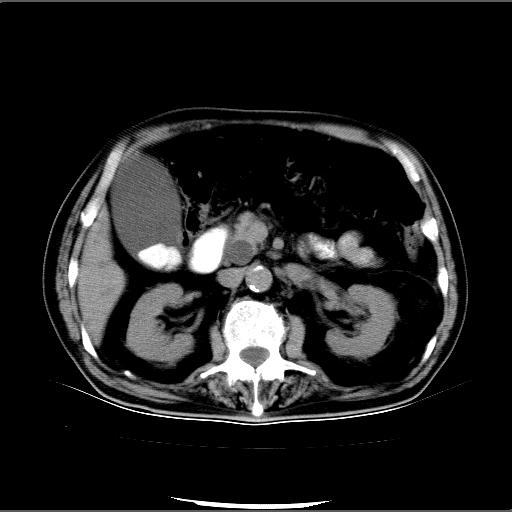

患者男82岁,黄染,发热10天,无腹痛。

1胆总管下端结石伴肝内外胆管扩张;2胆囊颈部结石伴胆囊积液

胆囊多发结石,胆囊积液;胆总管中下段结石,中上段扩张。

胆总管下段结石伴胆道系统扩张;胆囊炎伴胆囊结石.

有时胆总管下段结石的密度并不是均匀的高密度,而是以高密度为主的伴中心等密度的混合物,这与胆道结石的多样性有关,少数时候诊断困难时应结合临床病史,症状等,还有增强扫描都可以帮助明确诊断!!常与胆道蛔虫伴钙化鉴别!

1、胆总管壶腹部结石并胆总管、胆囊及肝内胆管扩张。2、胆囊多发结石。3、两下胸膜局限性增厚。4、胃体部大弯侧胃壁稍厚,建议:多量饮水后增强ct扫描除外占位性病变。

此病例有结果了:患者术后为:胆总管下段结石伴胆道系统扩张;胆囊炎伴胆囊结石。

各位战友分析的都很正确,是一个典型的病例。